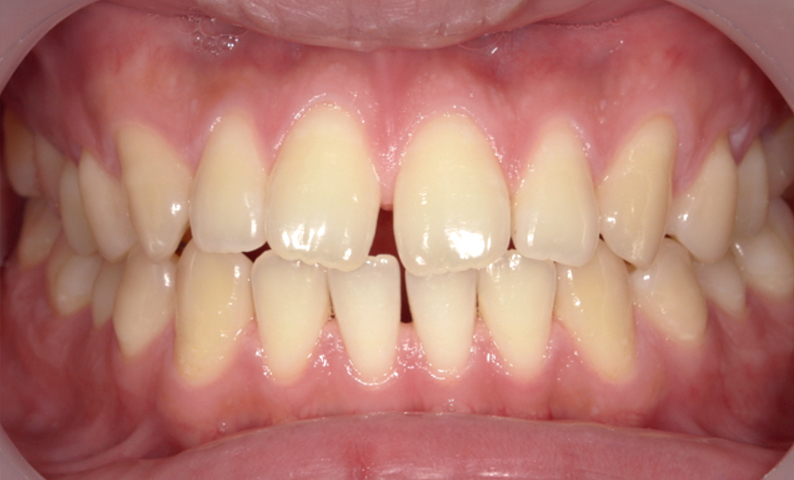

| 治療前 | 治療後 |

|---|---|

|